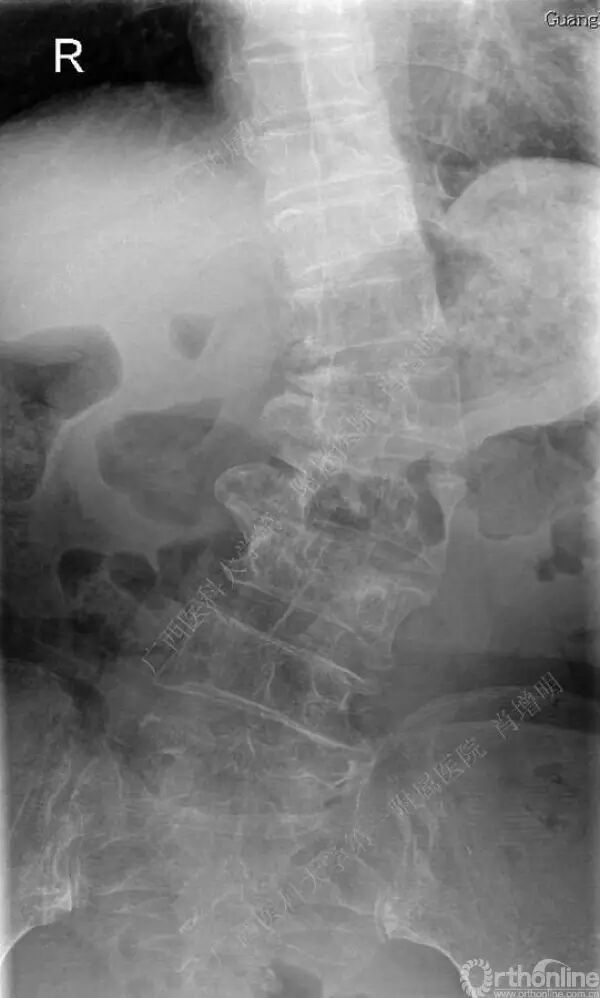

退变性脊柱侧凸是由于椎间盘退变后继发小关节退变,椎管和神经根管容积变化以及脊柱失稳,畸形等病理改变,以疼痛和神经压迫症状为主要表现的常见疾病。

退变性脊柱侧凸多发于50岁以上的中老年群体,是现代常见的老年疾病。多年来,针对该病的临床研究一直没有停步,广西医科大学第一附属医院肖增明教授细致地介绍了该病的诊疗进展。